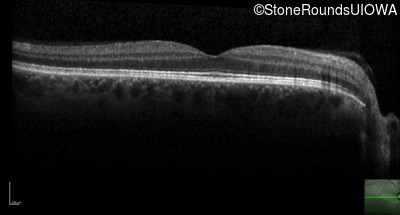

Optical Coherence Tomography - Left - Count Fingers 4' sc

Exemplar / OCT Stack